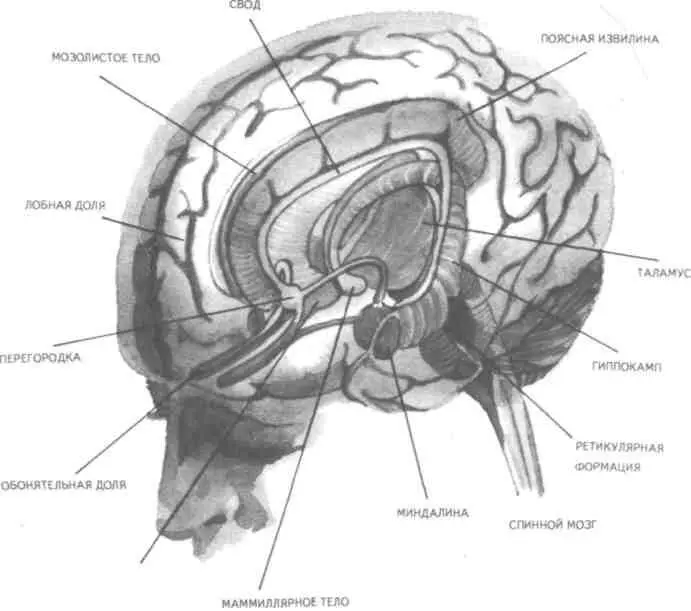

Кроме гиппокампа, в формировании и организации следов памяти участвует, по-видимому,

медиальная височная область мозга.

Таламическая область, как предполагают, нужна для первоначального кодирования некоторых

видов информации, получаемой через органы чувств. Что касается коры головного мозга, то есть

данные о ее связи с долговременной памятью.

целом. Что же касается мозговых структур, то, вероятно, нельзя назвать ни одной из них, которая

не имела бы прямого или косвенного отношения к удовлетворению потребностей. Но более всего

с ними, по-видимому, связаны таламус, через который проходят почти все нервные пути, идущие

в к.г.м. и обратно, подкорка, древняя, старая и новая кора.

Анатомо-фи-зиологической основой низших или простейших эмоций являются лимбические

структуры ц.н.с, а также процессы, происходящие в таламусе и гипоталамусе (рис. 24, 25).

Рис. 24. Важнейшие части мозга, образующие лимбическую систему. Можно видеть, что они

располагаются вдоль краев больших полушарий, как бы «окаймляют» их